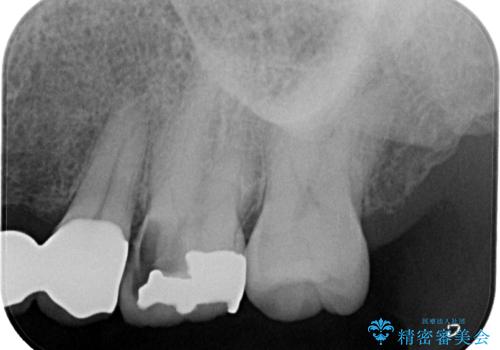

銀歯の下にまでむし歯が及んでおり、レントゲン写真からも神経組織に迫っている状態が確認されました。

稀に冷たいものがしみる程度で、術前診査では神経を全て取る可能性は低いと予想されましたが、一部切除する可能性が高いことを伝えた上で治療を行うこととしました。